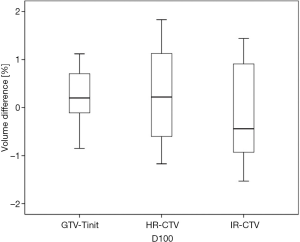

Among the 23 patients included in the present study, the mean tumor diameters were 68.35 cm3 at diagnosis and 29.63 cm3 at ICBT initiation. The mean tumor regression was 56.6%. The mean ± standard deviation (SD) HR-CTV D90 and D100 of the GTV-Tinit, IR-CTV, and parametrium were 69.58±4.94, 61.89±3.53, 54.16±4.01, and 55.71±2.73 Gyα/β=10, respectively, for DIR and 69.11±5.68, 61.55±4.15, 53.99±3.93, and 55.51±2.27 Gyα/β=10, respectively, for the conventional simple DVH parameter addition (Figures 3-5). No statistically significant differences were observed in the dosimetric parameters between the two calculation methods (Table 2). No systematic differences were observed between DIR-based accumulation and DVH parameter addition (P=0.11).

Contouring and reconstruction performed in the same image series allowed the dose to targets and organs to be directly calculated without any image fusion. However, the fusion uncertainties could translate into absorbed dose calculation when several image series were combined. For example, contouring was performed in one image series and reconstruction in another. Tanderup et al. reported that uncertainties resulted in a miscalculation of DVH dose parameters by typically 4% to 6% mm−1 of fusion error between CT and MRI (18). van Heerden et al. (19) recently used DIR to determine the absorbed dose distribution of daily image-guided adaptive EBRT and brachytherapy. The cone-beam CT of the first EBRT fraction and the brachytherapy planning MRI were registered by DIR. The cumulative dose to 2 cm3 with the highest dose (D 2 cm3) from EBRT and brachytherapy to the bladder and rectum were calculated and compared to those for direct addition, assuming a uniform EBRT dose (UD). The differences between UD and DIR were less than 3.9 GyEQD2. Our study only used CT images with the same field of view and slice thickness for fusion. The DIR-based DVH parameter values did not differ significantly from those derived from the conventional simple DVH parameter addition (Figure 3). According to the Groupe Européen de Curiethérapie and the GEC-ESTRO recommendations (10), the conventional simple DVH parameters for the target volumes and OARs in EBRT and each ICBT session were simply added to estimate the cumulative DVH parameters.